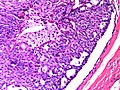

Intraductal papilloma. H&E stain. | |

| LM | true papillae (nipple-shaped structures with fibrovascular cores), intraductal proliferation of epithelial and myoepithelial elements, +/-hyalinization |

- True papillae - nipple-shaped structures with fibrovascular cores.

- Intraductal proliferation of epithelial and myoepithelial elements.[3]

- Lacks florid hyperplasia.[4]

- May degeneration and hyalinize to form a sclerosing papilloma.